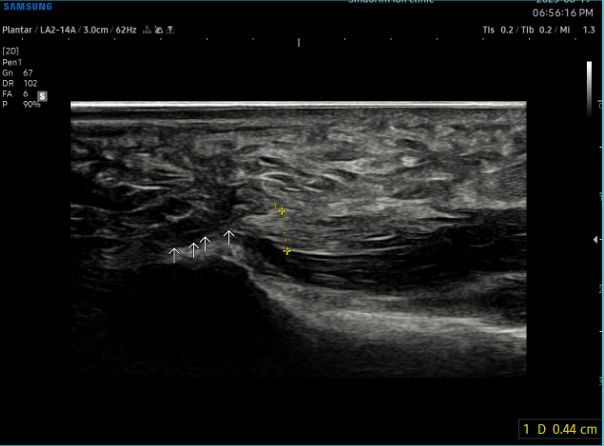

- 치료기간 : 25 .6 .19 ~ 25 . 10 . 23

- 치료횟수 : 15 회 (아피톡신+극초단파)

치료 전 (족저근막 두께 0.44~0.61cm)

치료 후 (족저근막 두께 0.33~0.36cm)